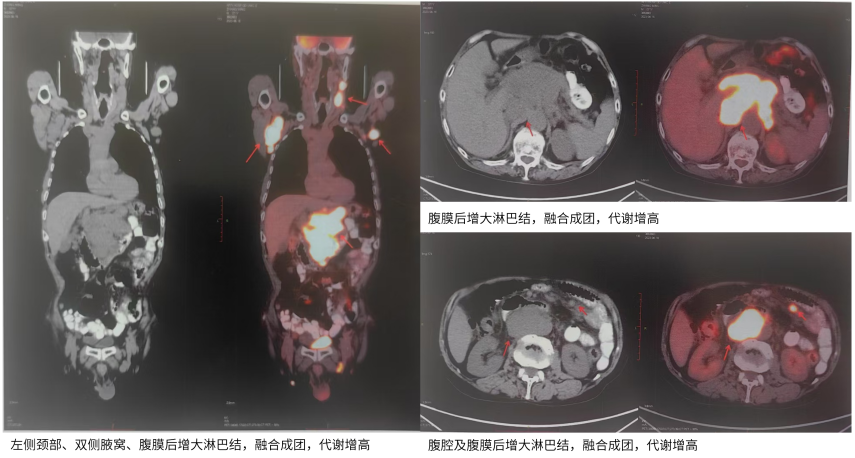

PET-CT(2023-06-19):1.左侧颈部Ⅰ-Ⅳ区、双侧腋窝、腹腔及腹膜后腹主动脉及下腔静脉周围、肠系膜区、右侧膈脚后、左侧髂外血管区、双侧腹股沟区多发增大淋巴结,部分融合成团,代谢增高,SUVmax约41.1,考虑淋巴瘤可能性大,建议获得病理结果;2.双肺慢性炎症或纤维灶;

图2 患者PET-CT表现